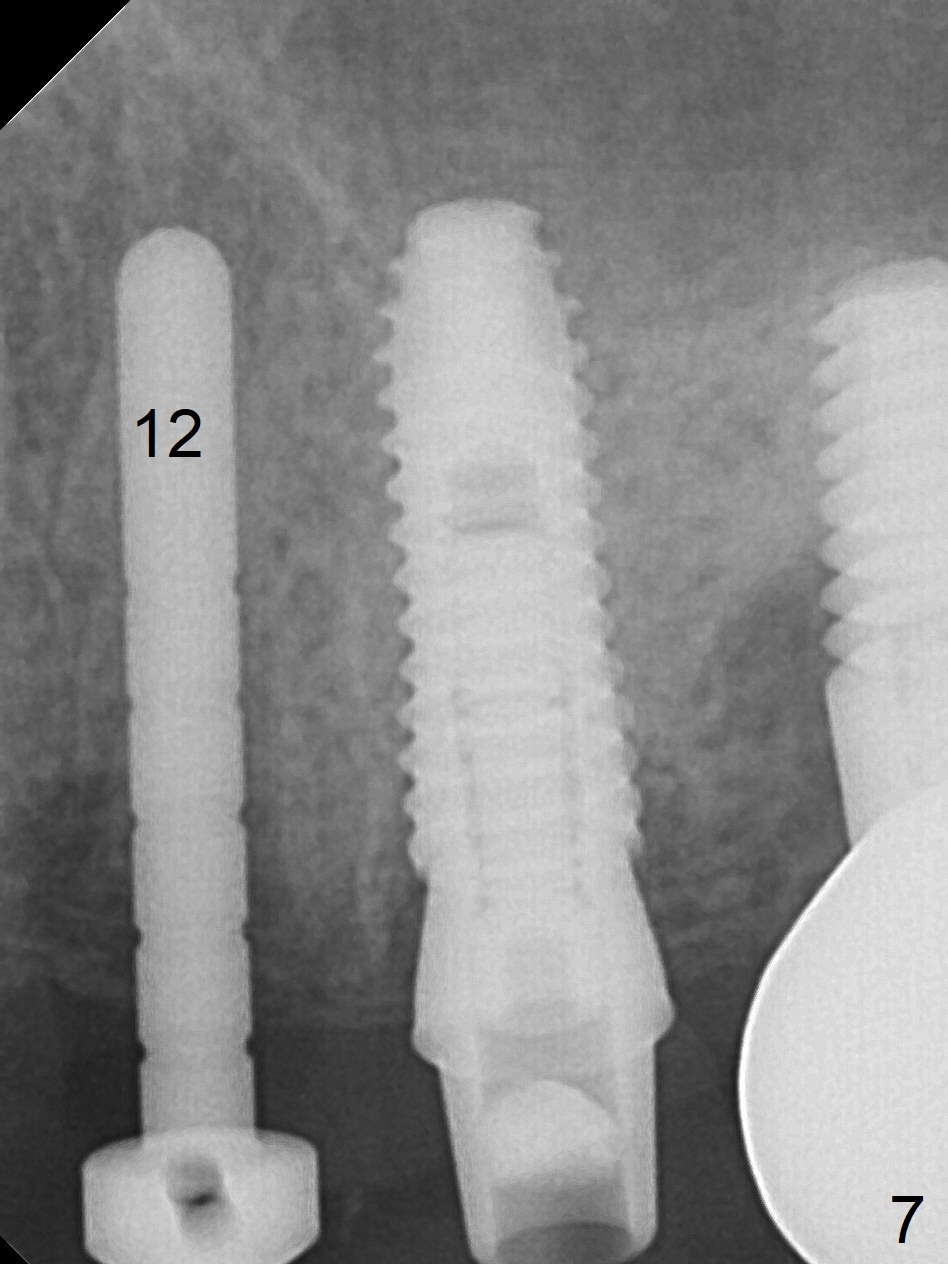

A parallel pin is not able to be inserted as deep as a 2 mm drill at #13 (Fig.1); at that time perforation of the sinus floor is not detected (arrowheads).

A Linderman bur is used to move the initial osteotomy distal. By the time of 3 mm in place, the trajectory seems to have improved; the sinus floor has been penetrated (Fig.2). Retrospectively, the parallel pin is not as sharp as the 2 mm drill to penetrate the perforated sinus floor (Fig.1).

The tooth #12 is found to have crack 3 months postop. Initial depth will be 17 mm for 3.8x13 mm implant (Fig.5; Clindamycin). The tooth has two roots (Fig.3). Osteotomy is to be created in the septum.

Preop photo shows palatally subgingival fracture (Fig.6). Initial depth is 15 mm at #12 after extraction (Fig.7) and then is extended to 17 mm. In fact the osteotomy is created in the palatal socket, since the septum is thin, while the buccal socket has its apical perforation. A 3.8x13 mm implant is placed (Fig.8); a 4.5x4(3) abutment and allograft are placed (Fig.9 *) prior to immediate provisional fabrication.